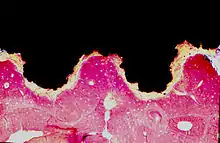

An osseointegrated implant is a type of implant defined as "an endosteal implant containing pores into which osteoblasts and supporting connective tissue can migrate".[2] Applied to oral implantology, this refers to bone grown right up to the implant surface without interposed soft tissue layer. No scar tissue, cartilage or ligament fibers are present between the bone and implant surface. The direct contact of bone and implant surface can be verified microscopically.

Osseointegration is a dynamic process in which characteristics of the implant (i.e. macrogeometry, surface properties, etc.) play a role in modulating molecular and cellular behavior.[14] While osseointegration has been observed using different materials, it is most often used to describe the reaction of bone tissues to titanium, or titanium coated with calcium phosphate derivatives.[15] It was previously thought that titanium implants were retained in bone through the action of mechanical stabilization or interfacial bonding. Alternatively, calcium phosphate coated implants were thought to be stabilized via chemical bonding. It is now known that both calcium phosphate coated implants and titanium implants are stabilized chemically with bone, either through direct contact between calcium and titanium atoms, or by the bonding to a cement line-like layer at the implant/bone interface.[16][17] While there are some differences (e.g. like the lack of chondrogenic progenitors), osseointegration occurs through the same mechanisms as bone fracture healing.[18][19]

For osseointegrated dental implants, metallic, ceramic, and polymeric materials have been used,[2] in particular titanium.[20] To be termed osseointegration the connection between the bone and the implant need not be 100%, and the essence of osseointegration derives more from the stability of the fixation than the degree of contact in histologic terms. In short it is a process where clinically asymptomatic rigid fixation of alloplastic materials is achieved, and maintained, in bone during functional loading.[21] Implant healing time and initial stability are a function of implant characteristics. For example, implants using a screw-root form design achieve high initial mechanical stability through the action of their screws against bone. Following placement of the implant, healing typically takes several weeks or months before the implant is fully integrated into the bone.[22][23][24] First evidence of integration occurs after a few weeks, while more robust connection is progressively effected over the next months or years.[25] Implants that have a screw-root form design result in bone resorption followed by interfacial bone remodeling and growth around the implant.[26]

Implants using a plateau-root form design (or screw-root form implants with a wide enough gap between the pitch of the screws) undergo a different mode of peri-implant ossification. Unlike the aforementioned screw-root form implants, plateau-root form implants exhibit de novo bone formation on the implant surface.[27] The type of bone healing exhibited by plateau-root form implants is known as intramembranous-like healing.[26]